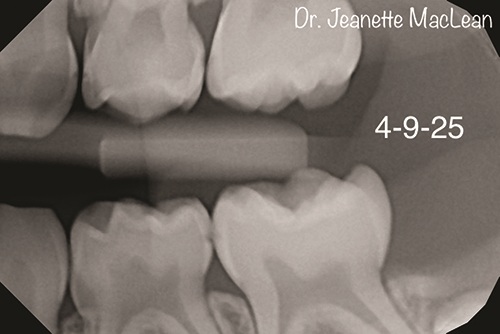

Figs. 1a and 1b: Bitewing radiographs of a second opinion patient (DEXIS Titanium imaging).

Figs. 2a and 2b: Overjet identifies incipient caries lesions, highlighted in yellow. Surgical intervention is not indicated at this time. Nonsurgical treatment with silver diamine fluoride is offered and accepted by parent.